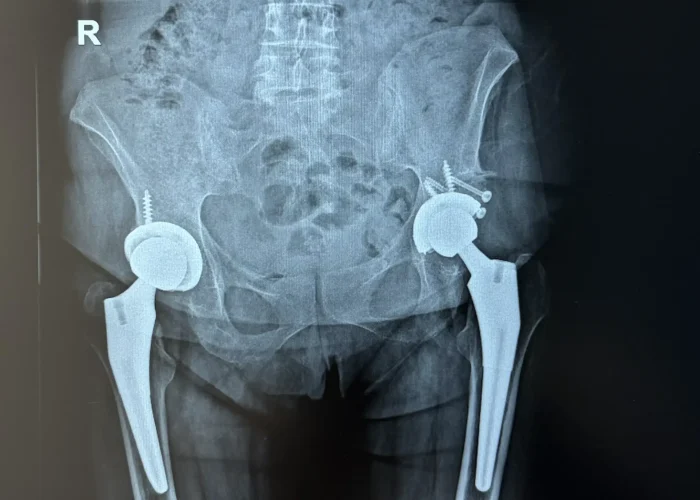

Pacienta, în vârstă de 56 de ani, s-a prezentat cu displazie coxală severă la șoldul stâng și coxartroză avansată la șoldul drept, asociate cu o scurtare a membrului inferior de aproximativ 2 cm.

După o evaluare atentă și planificare chirurgicală individualizată, am decis efectuarea unei artroplastii totale de șold bilateral, în doi timpi operatori, la un interval de aproximativ două luni între intervenții.

• Pacienta și-a recăpătat mobilitatea completă și a renunțat la sprijinul la mers.

• Calitatea vieții s-a îmbunătățit semnificativ, putând relua activitățile cotidiene fără durere.